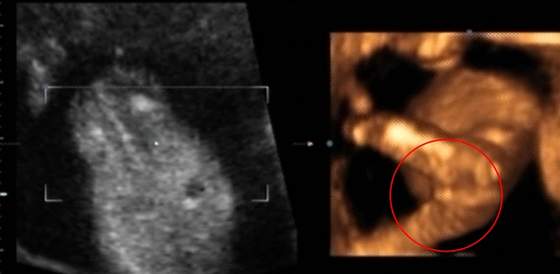

Mam dla Was poniedziałkową zgadywankę: któż to u mnie zamieszkuje? Wklejam printscreeny z filmiku, z "newralgicznymi miejscami" ;-) Dodam, że ja nie wiem, usłyszałam "chyba..."

To jak, zgadujecie?

Araki, mi się wydaje, że tam siusiaczka widać, ale głowy obciąć nie dam. Pisz, nie trzymaj w niepewności. edytuję: jeszcze raz spojrzałam i nie wiem. :-D

Araki mi się wydaje ze na 1 foto widać coś jakby wargi sromowe ale głowy nie dam uciąć :-p i jeszcze na którymś widać podobnie ... Mów szybko czekamy :tak:;-)

jeszcze raz zerkam 3,5 i 6 tez wygląda na wargi tak teraz daje 89 % ze to dziewczynka powiedz czy zgadłam